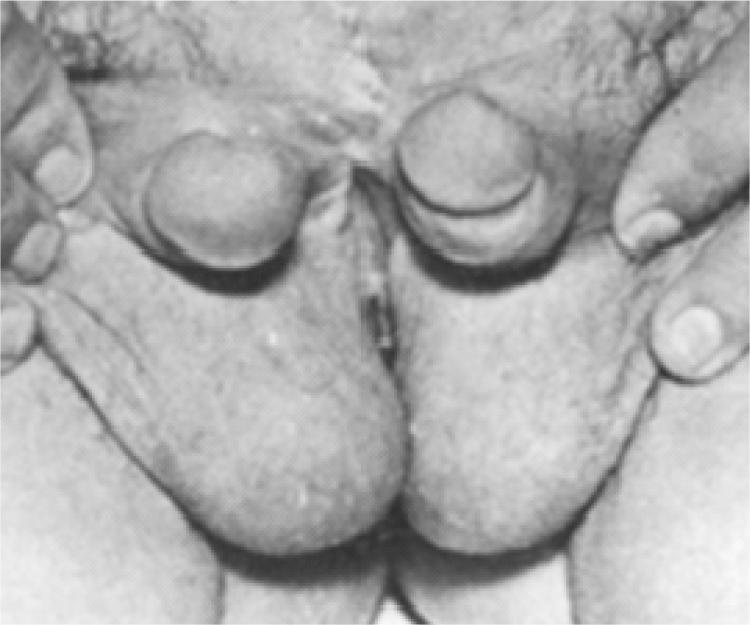

In this report we discuss six patients with diphallus which evaluated retrospectively. Five patients had complete diphallia, and one had bifid diphallus. Meatus was normal in 3, hypospadiac in 2, and epispadiac in one patient. The most common associated anomaly was bifid scrotum (5 cases), and other common anomalies consisted of bladder duplication (3 cases), imperforate anus (2 cases), and hypospadias (2 cases). Phalloplasty was performed for all but one.

在本报告中,我们回顾性地讨论了6例双阴茎患者。5例为完全性双阴茎,1例为阴茎分叉。尿道口正常者3例,尿道下裂者2例,尿道上裂者1例。最常见的相关畸形是阴囊分裂(5例),其他常见畸形包括膀胱重复畸形(3例)、肛门闭锁(2例)和尿道下裂(2例)。除1例患者外,其余患者均接受了阴茎成形术。